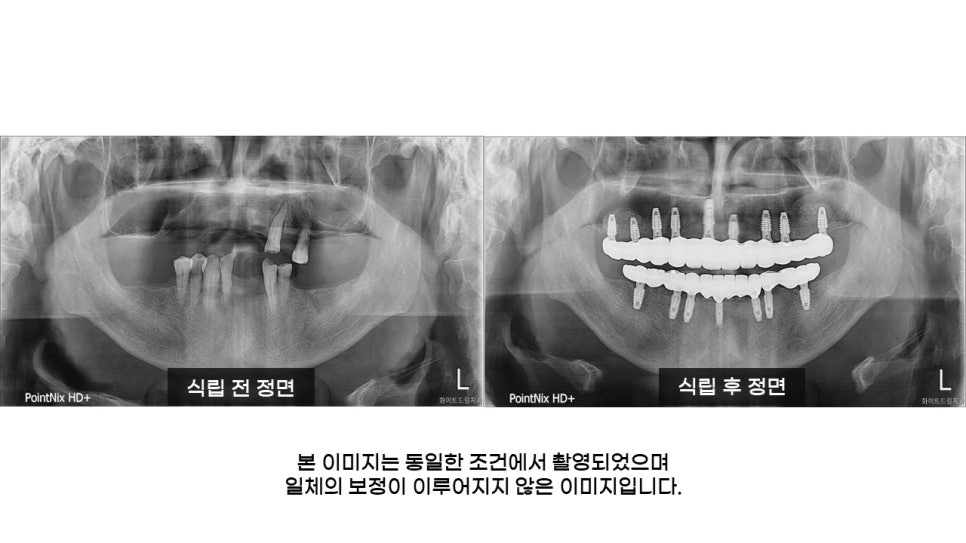

환자분의 식립 전 정면, 상악, 하악 사진을 살펴보면 치주질환 등으로 인해 뼈의 양이 충분하지 않아 잇몸뼈가 무너진 상태이셨으며, 상악은 대부분의 치아가 소실되어 있었습니다.

컴퓨터 모의진단으로 맞춤형 치료 계획을 수립한 결과, 남아 있는 치아 전체를 발치하고, 상악은 9개 임플란트를 식립하여 12개의 치아를 만들어 드리고, 하악은 7개 임플란트 식립 후 12개의 치아를 만들어 드리는 임플란트 식립을 진행했습니다.

마지막으로, 상악 좌, 우측 상악동 거상술과 상, 하악 치조골 이식을 동반한 임플란트 식립 후 최종 결과물 입니다.

상악과 하악 모두 자연치와 유사하게 식립되어졌으며, 9, 7개 임플란트 식립 후 나머지 4, 7개 치아는 치료기간을 단축해드리고 비용 부담을 줄여드리기 위해 브릿지를 사용해드렸습니다.